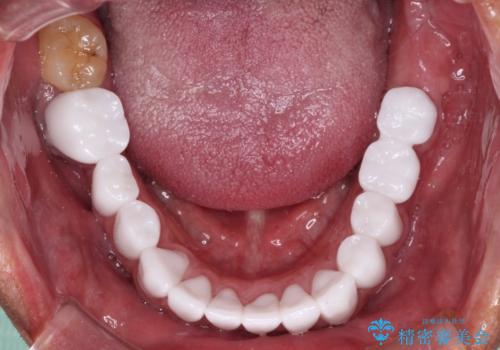

本来、あまりにも不自然な歯となるため、フルジルコニアクラウンを前歯に使用することは、咬合力が強すぎる場合を除き、ほとんどありません。

それでも、色調、形態ともに不自然なくらい真っ白な歯をご希望でしたので、患者様には大変満足していただきました。